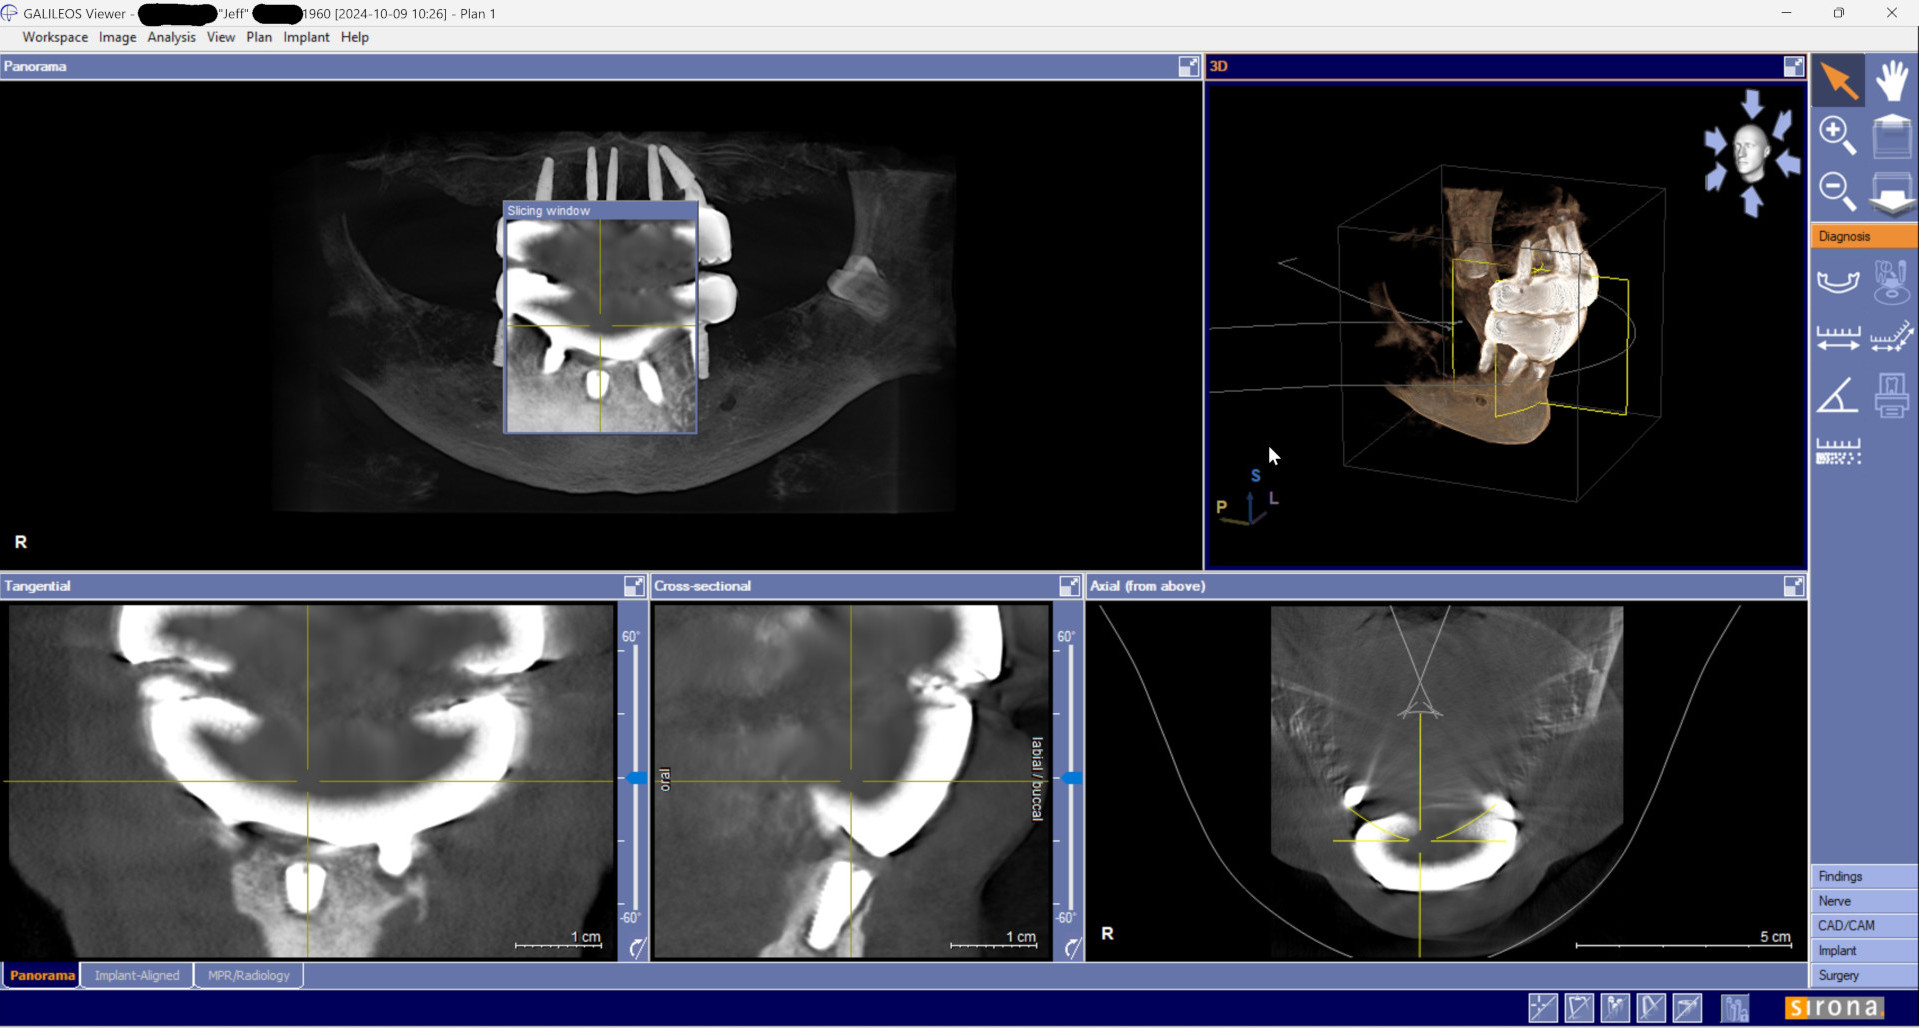

Earlier I mentioned that after trying to ignore the problem that the Michigan dentist had found two weeks earlier, Dr Shobhit Bansal grudgingly did a CT on September 12, 2024, then admitted there was a problem but tried to downplay it. Then Bansal specifically told me that everything else with the All on 4 was perfect.

The near total lack of bone at the right lower rear implant, and all the other problems with the implants, already existed when the first periodontist took a CBCT and xrays on October 9, 2024, less than one month after Bansal said everything was perfect. Clearly all those problems did not magically develop overnight.

After reviewing CBCT and additional high definition xrays of each implant, a prosthodontist with 40 years experience wrote in his report:

"... the last implant on the lower right side has practically no bone, the last implant on the lower left has about 70-80% bone loss. Both implants should be removed. One implant in the middle is not being used ... "

There are several issues with all of the implants, from problems with their locations, problems with mismatched heights from one implant to another, problems with their depth requiring gum grafts as there is no attached gingiva, problems with two of the upper implants apparently touching each other per periodontist report, a few other issues, and all seem to have some level of bone loss around the implants.